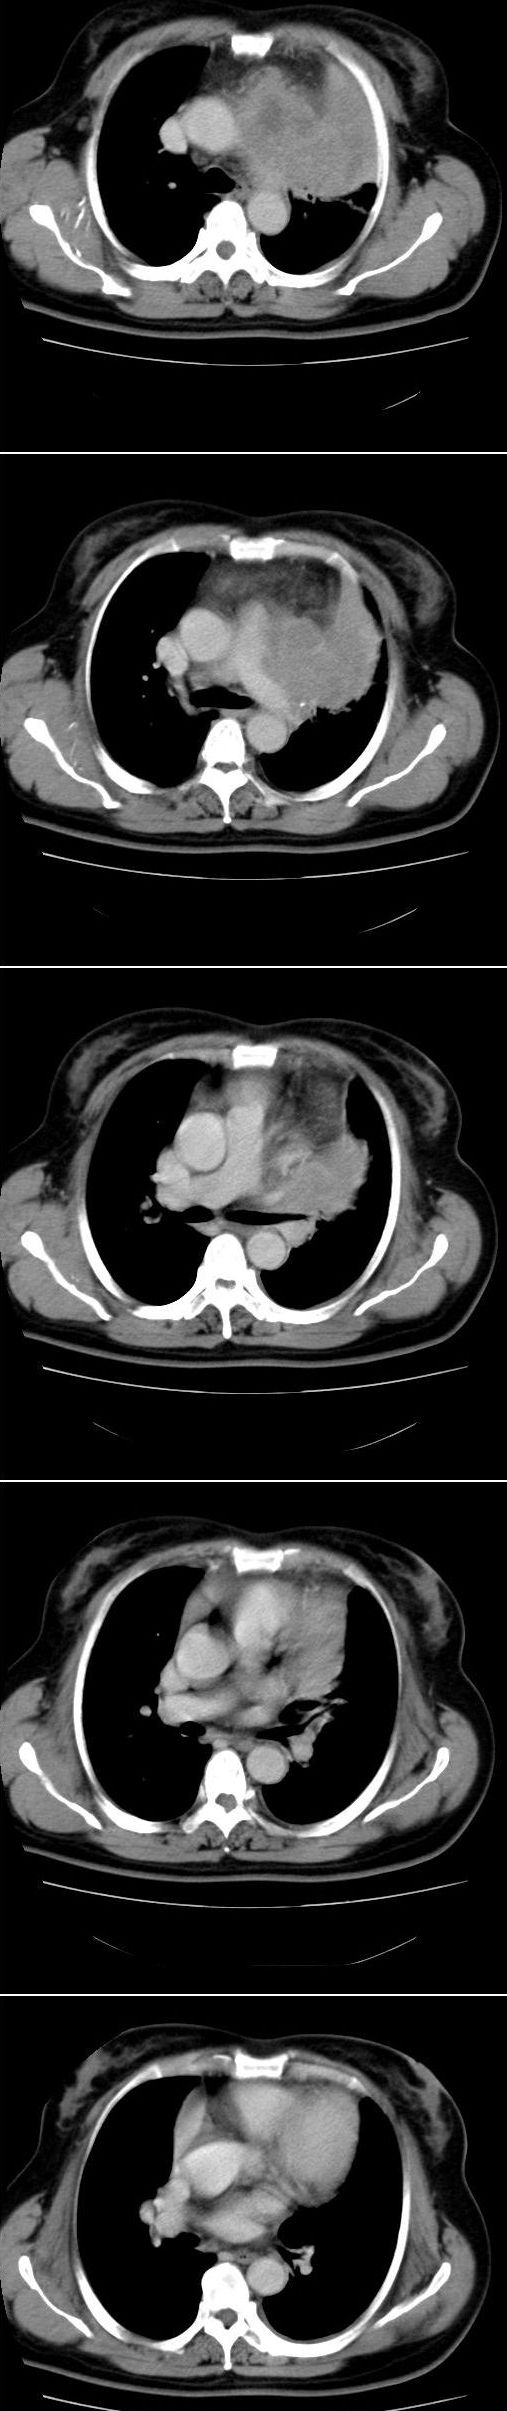

标题: CT13028:女,56岁。咳嗽、气促一月,咳血一周。CT值增加约30 [打印本页]

标题: CT13028:女,56岁。咳嗽、气促一月,咳血一周。CT值增加约30

左上肺肿块伴阻塞性改变,考虑肺癌可能大

感觉病灶主要来源于前上纵隔,向周围浸润,考虑为侵袭性胸腺瘤。

考虑左上肺癌(周围型)伴左肺门及纵隔转移(主肺动脉窗旁病灶可能为肿大并坏死的淋巴结),不除外纵隔型肺癌

软组织肿块,应该有肺不张(因为左膈及脾脏\\胃抬高明显):考虑中央ca

支持纵隔旁型肺癌伴主动脉弓\\主肺动脉及左侧头壁动脉受侵.

考虑左肺中心性肺癌并纵隔淋巴结转移,累及左肺动脉及左侧头臂静脉.但不除外纵隔恶性肿瘤累及肺组织.

考虑左肺中心性肺癌并纵隔淋巴结转移,纵隔恶性肿瘤累及肺组织的可能性小,因为后者一般不会导致横膈上抬。

考虑左侧中央型肺癌伴左肺上叶肺不张及前纵隔淋巴转移。

1)考虑为:左肺上叶中心型肺癌伴左肺上叶阻塞性肺炎、节段性肺不张,左肺门及纵隔淋巴结转移。2)左侧少量胸腔积液。